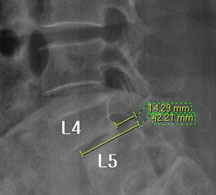

뼈가 앞으로 밀려나갔다고 하니 척추가 당장이라도 주저 앉을 것 같고, 한없이 밀려나갈 것 같지만 일반적으로 밀려나간 뼈는 대부분 1-2단계(25~50%) 정도 밀려나간 상태에서 안정화되는 경향을 보이기 때문에 그 자체로는 문제가 되지 않습니다.

즉, 척추전방위증은 통증을 일으키는 원인질환(디스크, 협착증)을 치료하는 것이 척추 뼈를 더 이상 앞으로 밀려나가지 않게 하는 치료라고 볼 수 있습니다. 모커리는 뼈가 50% 이상 밀려나간 2단계의 척추전방위증도 비수술로 치료하고 있으며, 이러한 한방치료 효과를 객관적으로 검증하여 유명학회 및 논문에 계속해서 발표하고 있습니다.

모커리한방병원은 2013년 1월부터 2014년 3월까지 척추전방위증으로 입원한 환자를 대상으로 치료 전•후를 비교분석한 결과, 복합척추치료 약 3주 후 환자가 느끼는 허리와 엉덩이 통증지수가 7.1에서 3.1로 줄었으며, 통증 없이 걸을 수 있는 거리 역시 193m에서 568m로 약 3배 가량 증가했습니다. 이번 연구결과를 계기로 50% 정도 밀려나간 2단계의 척추전방위증 환자들도 수술 없이 충분히 치료될 수 있다는 것이 객관적으로 검증되었습니다.

모커리한방병원은 50% 정도 밀려나간 2단계의 척추전방위증 환자를 대상으로 약 3주간의 입원집중치료를 실시한 결과, 입원 시보다 80% 이상 통증이 감소되어 치료되었습니다. 통증 없이 걷는 시간도 약 3배 정도 증가되어 단기간에 수술 없이 높은 치료효과가 나타났다는 것을 대한침구의학회에 발표하였습니다. 50% 정도 밀려나간 2단계의 중증 척추전방전위증 환자이면서 심한 척추협착증 증상을 나타내는 환자를 치료한 결과입니다.